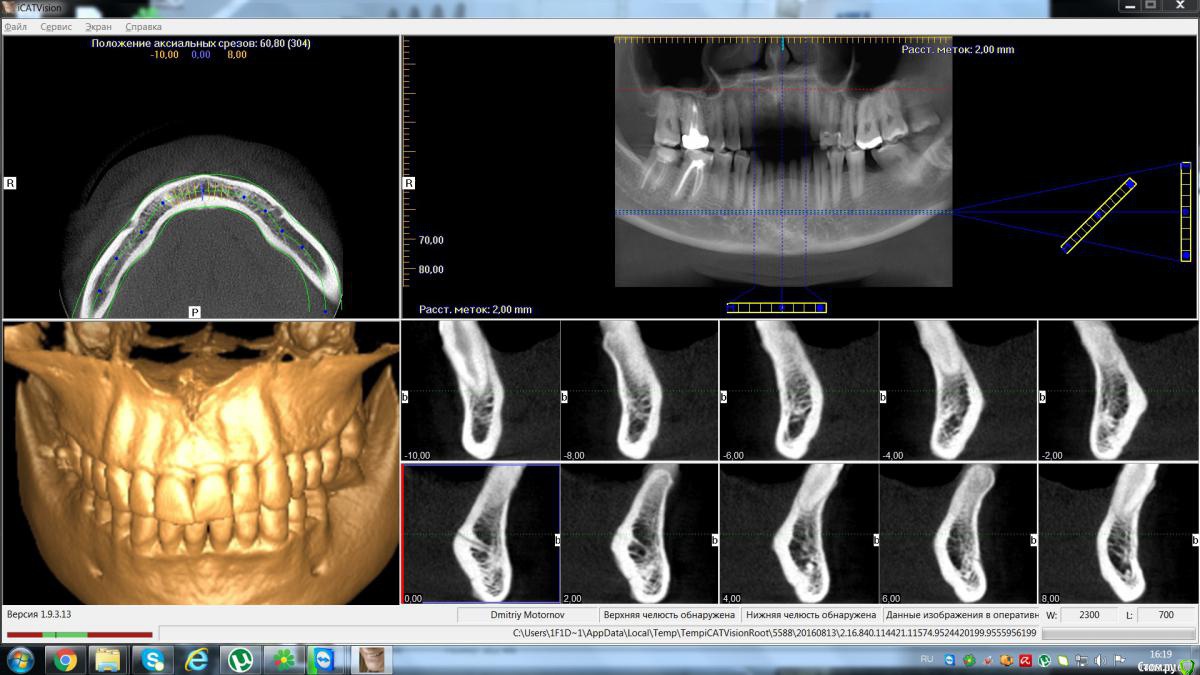

Maktub Опубликовано 13 августа, 2016 Автор Поделиться Опубликовано 13 августа, 2016 Сделал кт, дали диск с программой. Снимок оттуда выдирается или нет? Ссылка на комментарий

Maktub Опубликовано 14 августа, 2016 Автор Поделиться Опубликовано 14 августа, 2016 Не нашел, где там импорт снимка,сделал скриншот. Почему программа запускается только с диска, скопированная не работает? Ссылка на комментарий

Maktub Опубликовано 14 августа, 2016 Автор Поделиться Опубликовано 14 августа, 2016 вот Ссылка на комментарий

Maktub Опубликовано 15 августа, 2016 Автор Поделиться Опубликовано 15 августа, 2016 По кт такие жерекомендации? Ссылка на комментарий